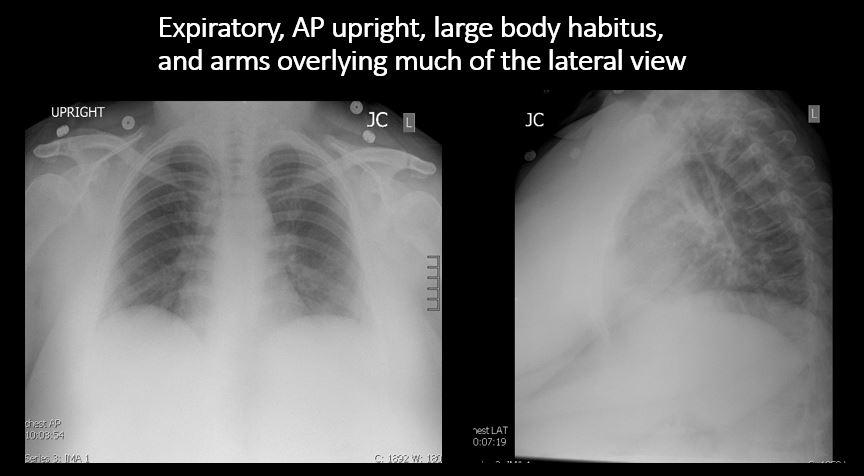

The exam is expiratory, rotated, over or under penetrated, or limited by overlying structures or soft tissues, body habitus, patient positioning, or motion. [Yes/No]

The lungs are hyperinflated or underinflated generally or segmentally. [Yes/No]